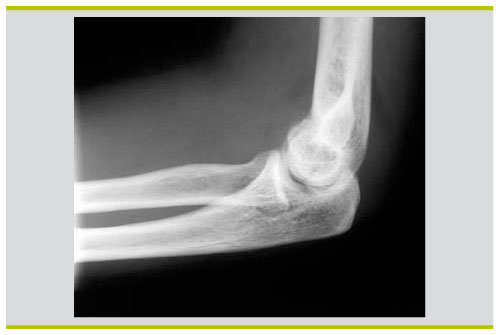

Il est important de différencier la contusion du coude, en particulier la blessure au coude chez l'enfant, des entorses, des dislocations et des fractures L'enfant est très clairement vu limiter les mouvements de flexionextension, le bras souvent blessé, il essaie de maintenir sa main, en plus d'un œdème osseux de coude cassé est. Fracture pilon tibial Fracture bimaléollaire avec luxation Fracture de la cheville Fracture tête radiale coude droit avec prothèse inerte Fracture du lifranc avec fracture déplacée du premier cunéiforme Marcher correctement apres fracture Tibia/Peroné Plus de sujets relatifs à. L’entorse légère Douleur immédiate, qui peut disparaître rapidement mais revenir de manière lancinante au bout de quelques heures Les mouvements sont possibles;.

Un traumatisme isolé du coude doit faire rechercher une lésion associée à l’épaule, au bras, à l’avantbras et au poignet a) ostéoarticulaire b) vasculonerveuse Le coude doit être mobilisé précocement à cause du risque de raideur posttraumatique ou postopératoire 21 Luxation du coude. > au développement d’une l’arthropathie acromioclaviculaire Traitement chirurgical des entorses acromioclaviculaires de stade 4 et 5 Dans les stades 4 et 5 les l’ensemble des attaches ligamentaires sont rompues et entraîne une perte de contact entre acromion et clavicule. • au pli du coude (tendinite du biceps) • à l’arrière du coude (tendinite du triceps) Pour soigner une tendinite du coude, il faut appliquer les remèdes naturels suivants 1) Mettre au repos le coude et le poignet Pour commencer, vous devez arrêter toutes les activités augmentant la douleur.

Examen clinique du coude pour entorse du ligament latéral interne https//wwwsportsanteconseilorg/support/helpus. L'entorse est un étirement ou une déchirure d'un ou de plusieurs ligaments d'une articulation Les principaux symptômes d'une entorse sont la douleur et l'inflammation locale puis un oedème, des spasmes peuvent aussi intervenir Dans tous les cas, c'est le froid qui est recommandé, il ne faut pas mettre de chaleur ni masser Mettez votre articulation et vos muscles alentour au repos et. Conduite à tenir (2) • Si le coude ne se reluxe pas en extension – Stabilité au testing • Attelle en flexion 90° pendant quelques jours puis rééducation – Instabilité au testing • Orthèse articulée maintenant l’avantbras en pronation • Si le coude se reluxe en extension – Immobilisation trois semaines en flexion.

Entorse au coude Avezvous une douleur au coude suite à un accident soit un coup ou une torsion La douleur peut être à l’intérieur, à l’extérieur ou diffuse au niveau du coude. L’entorse du coude est la lésion des ligaments situées entre l’humérus et l’ulna (cubitus) au niveau du coude ou entre le radius et l’ulna (cubitus) Si l’entorse est importante, cela peut aboutir à la luxation du coude Comment apparaît une entorse du ligament collatéral médial du coude?. Les tendinites au coude ne touchent pas que les sportifs mais peuvent également survenir chez les personnes effectuant des mouvements répétitifs (menuisiers, maçons, jardiniers, etc) En effet, une sollicitation excessive des tendons entraîne des microt.